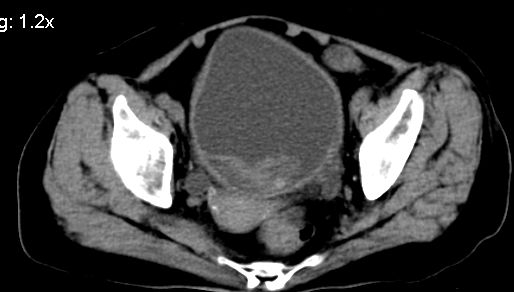

膀胱充盈可,壁光滑厚薄尚均匀,其内下方可见不规则的致密影,建议做膀胱镜检查

膀胱癌突破浆膜可能性大

考虑膀胱癌可能性大伴双侧输尿管下端扩张.

膀胱后壁见不规则致密影,我们遇到这样的病人都再做一次俯卧位扫描;排出膀胱内凝血块。

1.膀胱后壁见不规则致密影,占位?膀胱内凝血块?建议俯卧位扫描、膀胱镜检查.

2.双侧输尿管下段扩张.

膀胱三角区不规整软组织改变,双侧输尿管扩张,所以占位性病变肯定首先考虑,建议改变体位扫描除外游离血块影,但老年人出血原因一定要查明。